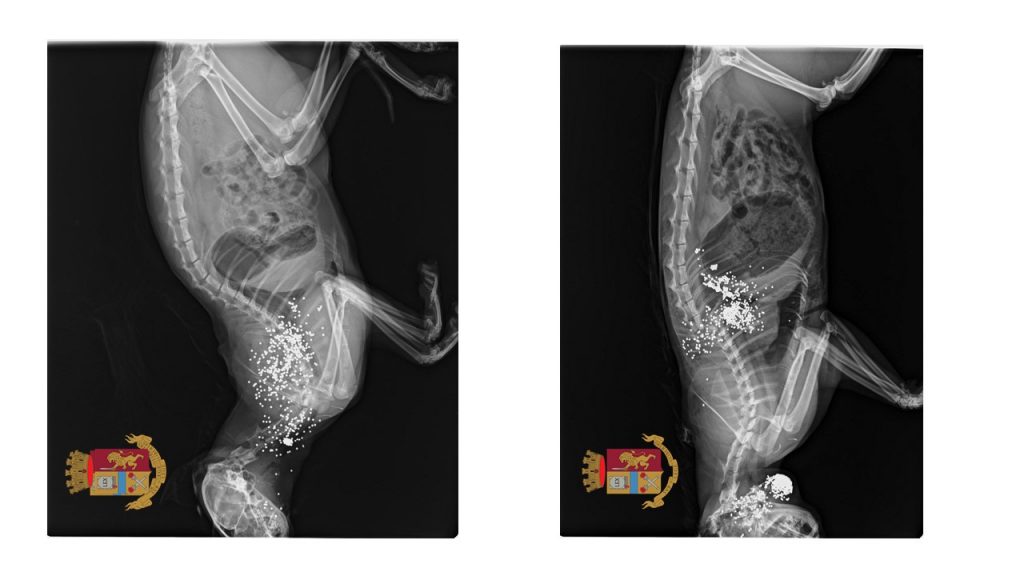

Secondo quanto emerso dalle investigazioni dei poliziotti l’uomo, titolare di porto di fucile per uso caccia, dopo aver ucciso a colpi di fucile caricato a pallini due gatti randagi che si aggiravano nei pressi della sua abitazione, si sbarazzava delle carcasse chiudendole all’interno di un sacco di plastica e gettando il tutto nell’immondizia.